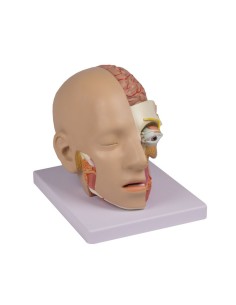

Découvrez le monde de l'anatomie avec des modèles anatomiques de précision

Bienvenue sur Tuttoanatomia.it, le portail de référence en Italie pour l'achat de modèles anatomiques, de posters, de lits portables, de simulateurs médicaux et de littérature spécialisée. Grâce à nos modèles anatomiques de pointe de 3B Scientific et Erler Zimmer, nous offrons une expérience d'apprentissage inégalée.

Des modèles anatomiques détaillés pour tous les besoins

Du crâne en 22 parties à verrouillage magnétique aux modèles de colonne vertébrale, des modèles d'articulation aux modèles de cœur, chaque pièce de notre collection est conçue pour une immersion totale dans l'étude de l'anatomie humaine. Nos modèles, réalisés à partir de scans d'os réels, garantissent une expérience tactile authentique et une fidélité de poids presque identique aux originaux.

Indispensables aux étudiants comme aux professionnels, nos modèles anatomiques sont des outils pédagogiques qui permettent d'observer les structures anatomiques avec précision, en évitant les dissections ou les études invasives. Ils sont également utiles pour expliquer les pathologies aux patients, ce qui rend la communication plus efficace et permet de gagner un temps précieux.